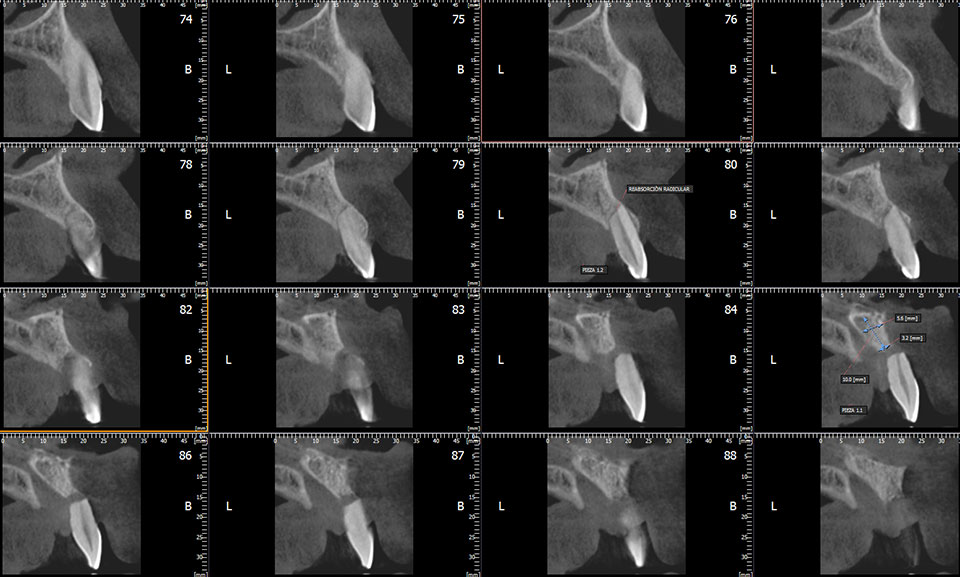

Cone Beam de alta resolución con FOVs múltiples. Reconstrucciones volumétricas para implantología, ortodoncia, endodoncia y cirugía maxilofacial.